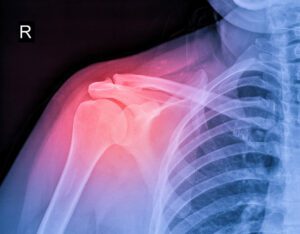

10 Symptoms Indicating You Might Need Rotator Cuff Surgery

The rotator cuff is a group of muscles and tendons that stabilize your shoulder and help you lift and rotate your arm. It is one of the most important yet vulnerable parts of your body, particularly for those who perform repetitive shoulder movements. Issues in your rotator cuff can lead to pain, Read More